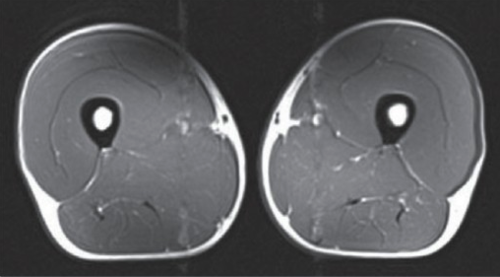

This image is an MRI – Cross-section mid-thigh of a 40 year old Triathlete:

The dark grey is muscles and white is fat